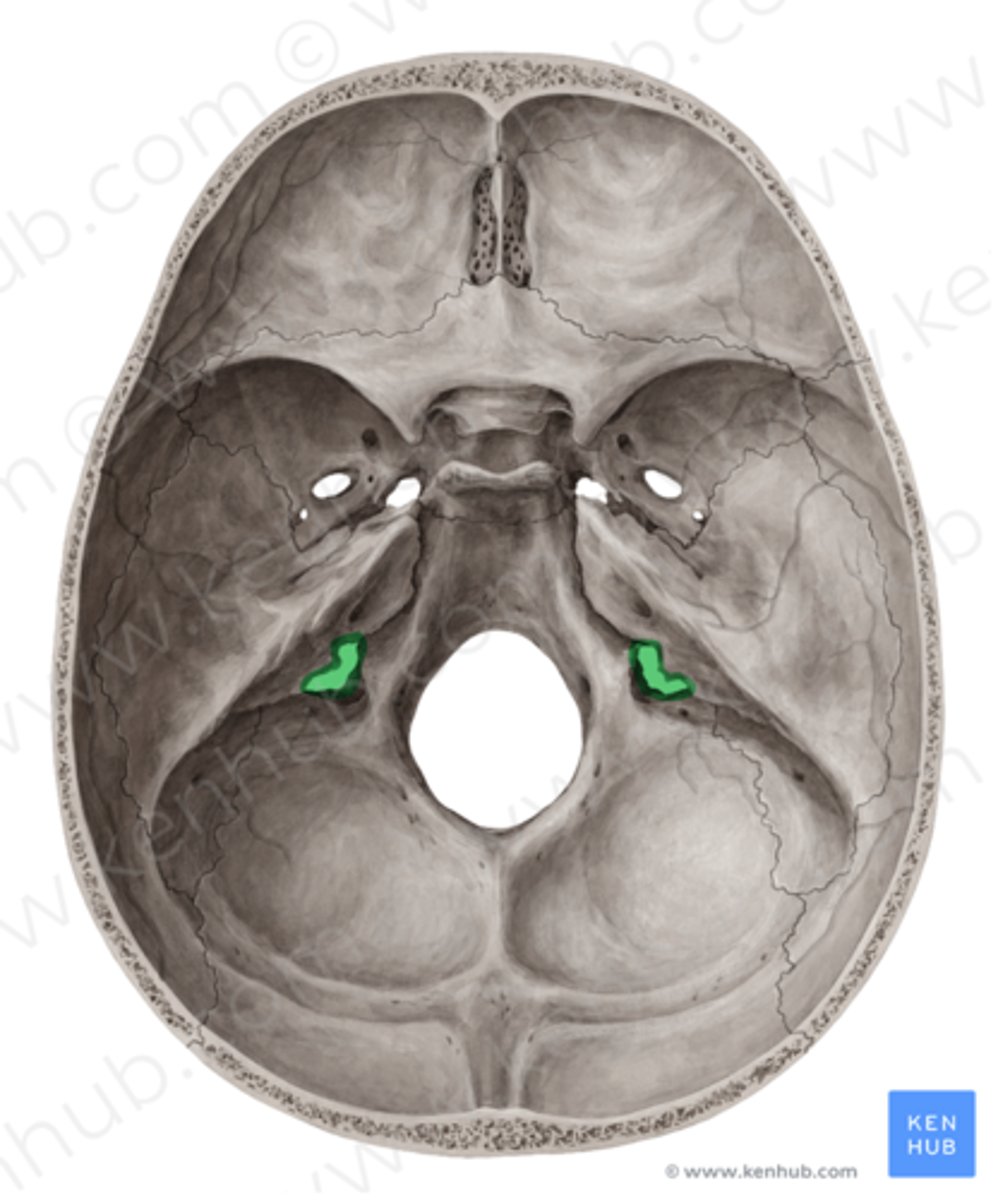

Basis carnii

Kaukolės pamatas

Foramen jugulare

Jungo anga

Foramen magnum

Didžioji anga